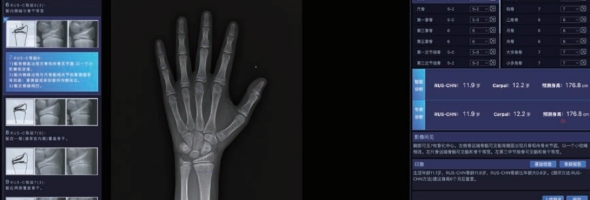

安智康生物自主研发的儿童手部X射线图像骨龄AI辅助评估软件,于2025年3月成功获批国家药品监督管理局三类医疗器械证(注册证编号:国械注准20253210620)。这也标志着,安智康生物成为国内同时具备骨龄检测硬件和骨龄AI软件三类医疗器械证的厂家!

儿童骨龄AI评估软件